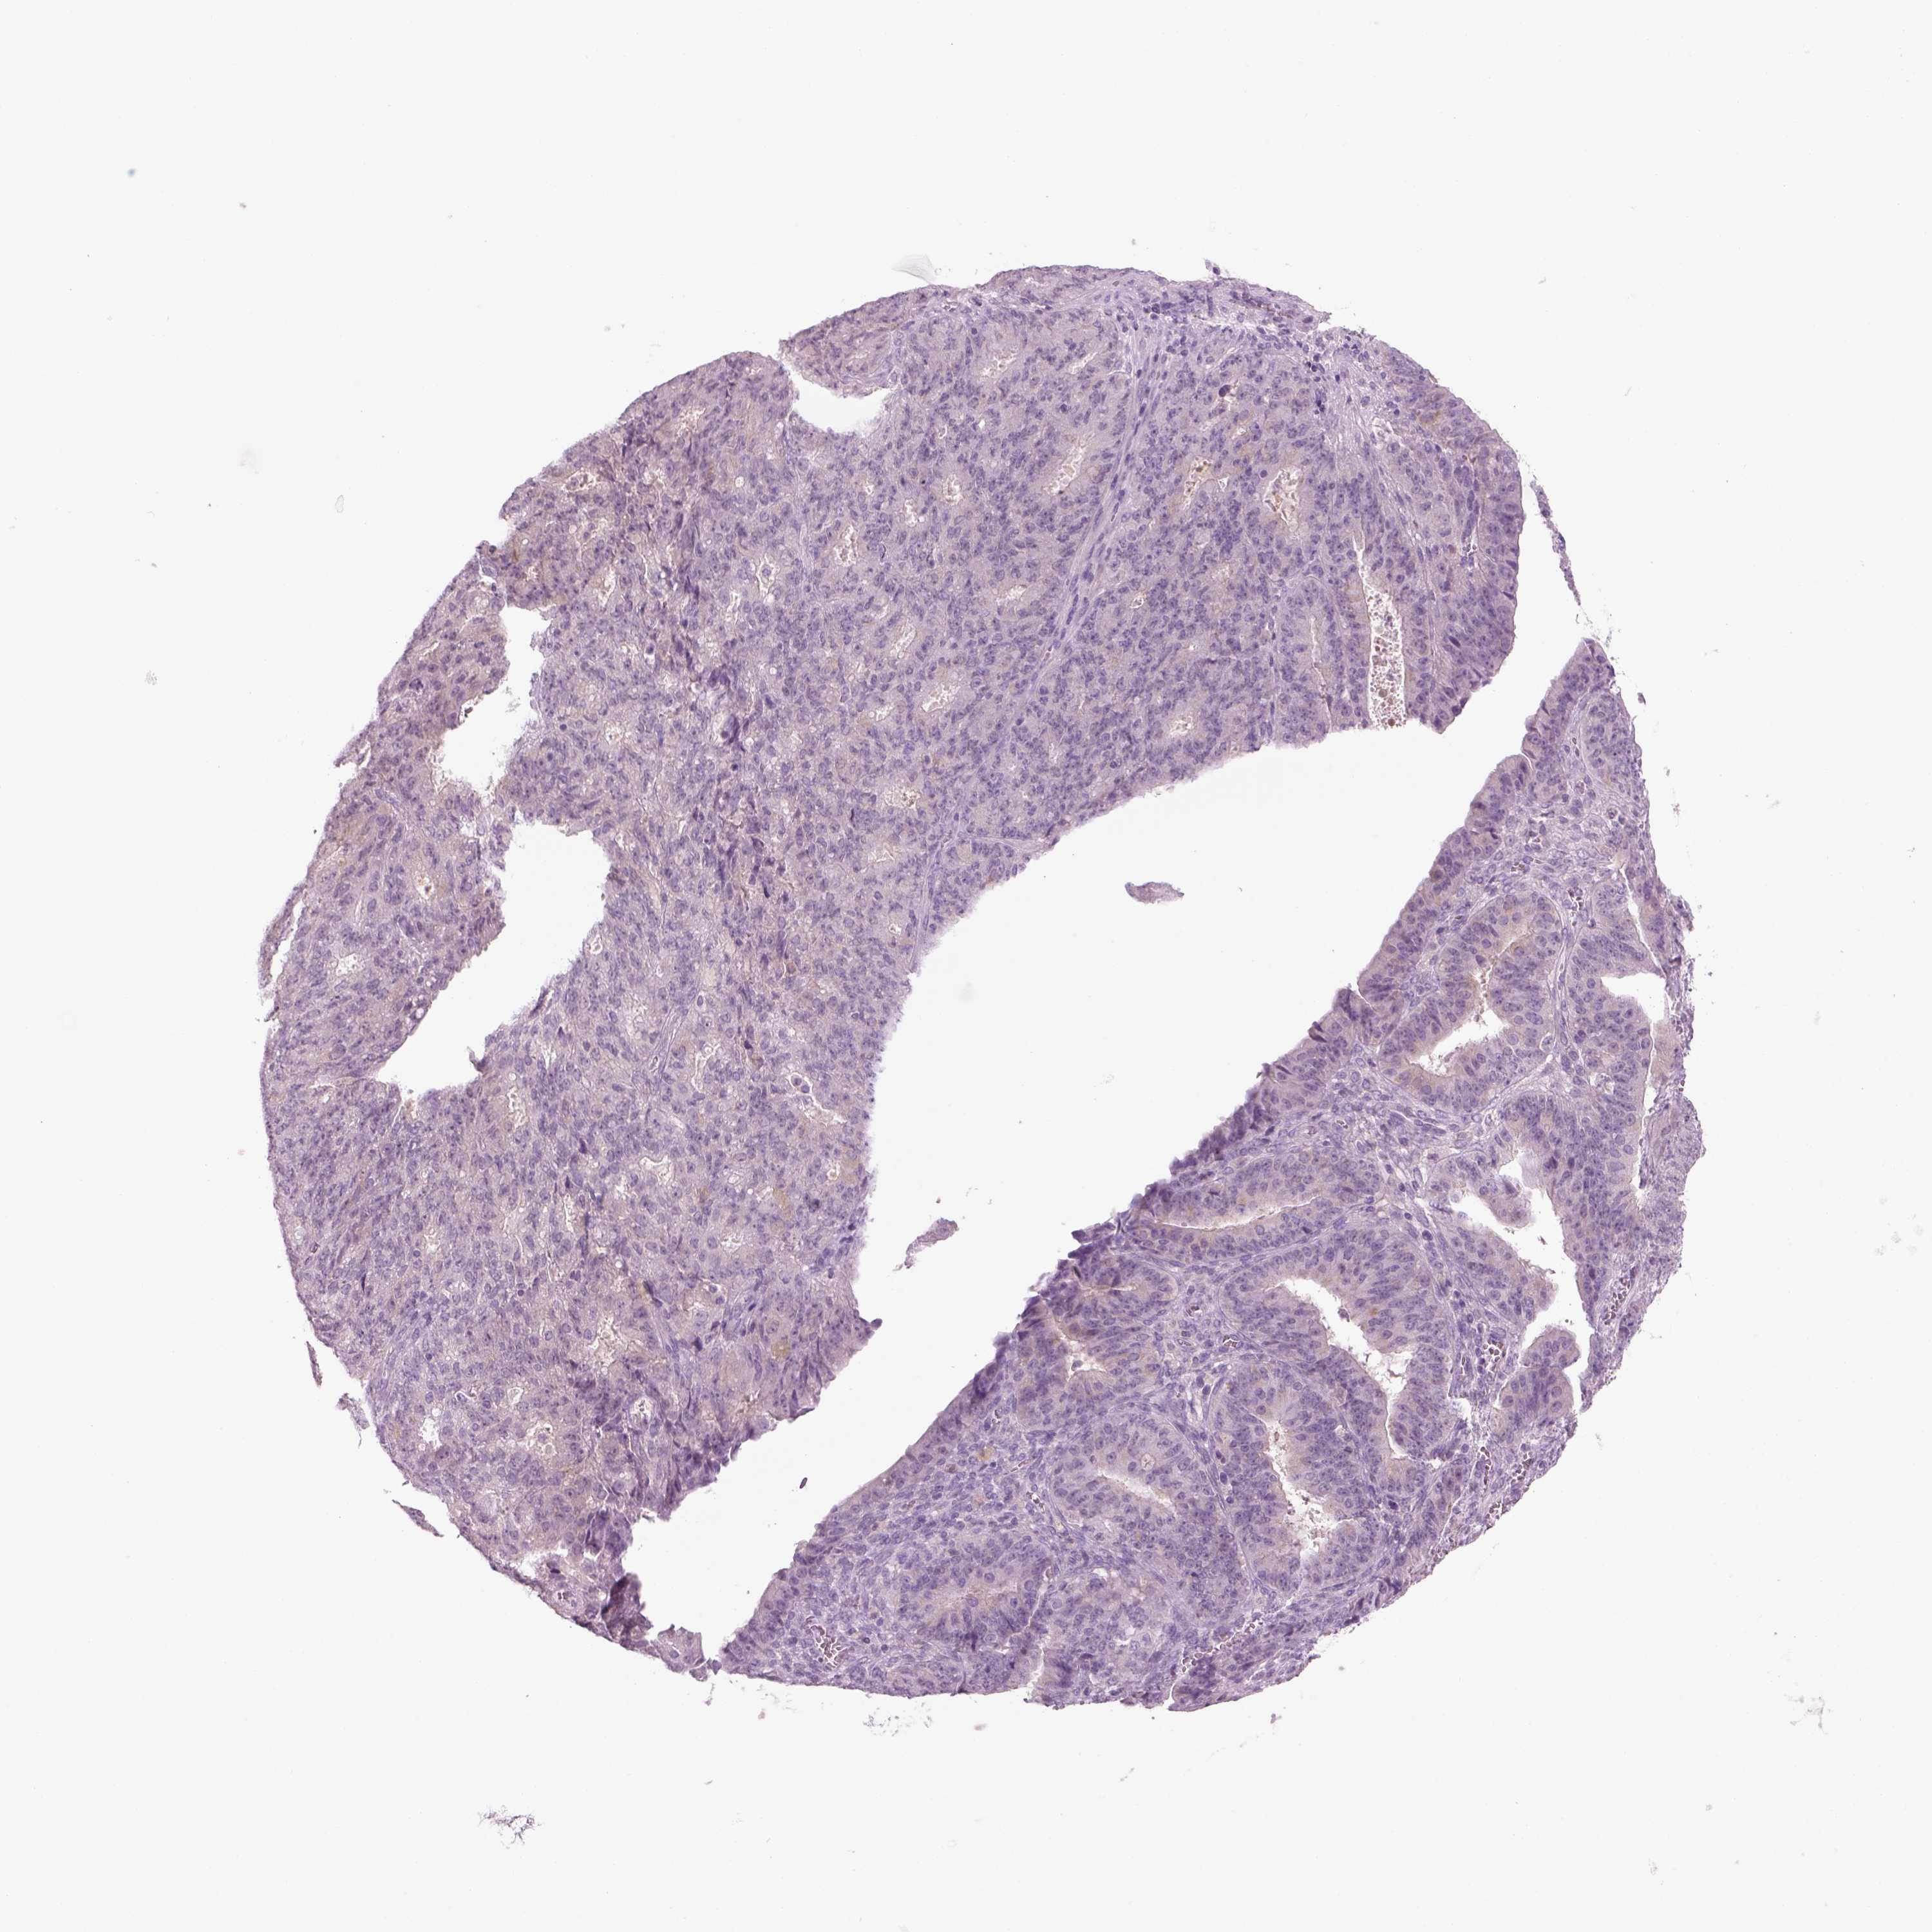

OVARIAN CANCER - Protein expressioni

A mouse-over function shows sample information and annotation data. Click on an image to view it in a full screen mode. Samples can be filtered based on level of antibody staining by selecting one or several of the following categories: high, medium, low and not detected. The assay and annotation is described here.

Note that samples used for immunohistochemistry by the Human Protein Atlas do not correspond to samples in the TCGA dataset.

Antibody stainingi

Antibody staining in the annotated cell types in the current human tissue is reported as not detected, low, medium, or high, based on conventional immunohistochemistry profiling in selected tissues. This score is based on the combination of the staining intensity and fraction of stained cells.

Each image is clickable and will lead to virtual microscopy that enables deeper exploration of all samples and also displays staining intensity scores, fraction scores and subcellular localization as well as patient and tissue information for each sample.

Antibody HPA073761

Cystadenocarcinoma, serous, NOS

Cystadenocarcinoma, mucinous, NOS

Carcinoma, endometroid